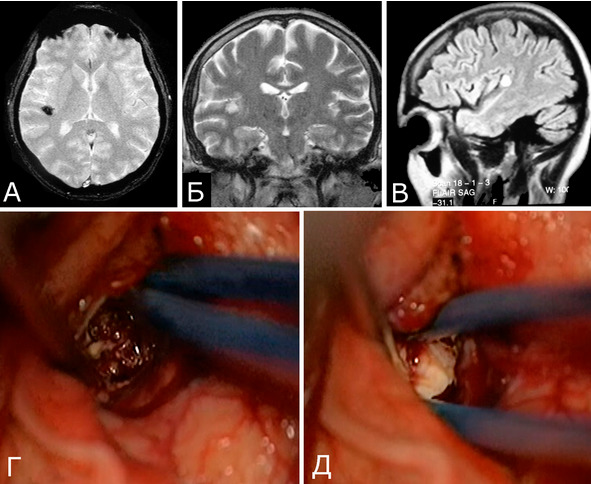

В небольшом числе случаев перифокальные изменения мозговой ткани отсутствуют (рис. 9).

Рис. 9. Б-ная М-на, 39 лет. Небольшая КМ в глубинных отделах задней верхней височной извилины справа. Клиническое течение: Редкие эпилептические припадки в течение 3-х лет. А, Б, В – КМ диаметром 1см, без явных признаков кровоизлияний (МРТ, режимы GRE, Т2, Flair, аксиальная, фронтальная, сагиттальная проекции). Г, Д – интраоперационные фото. В ходе операции нет визуальных признаков изменения мозговой ткани вокруг каверномы, мозг после удаления КМ имеет нормальную окраску